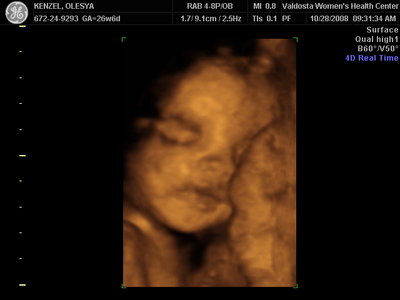

Ксюнь, а мы вообще не поняли. Она на всех фотках разная, да еще размытость такая. Пуповина то на носу болталась, то руками-ногами закрывалась. Главное что четкости нет совсем. Лоб у мужа тоже большой, а носы и губы зачастую на 3Д-4Д выходят разамазанно-пухло-приплюснутыми Поставлю для наглядности фотку моей средней-Джианки с 3Д УЗИ, там видно черты намного лучше и она на себя ту похожа сейчас, хотя родилась мне совсем на фото УЗИ не казалась похожей.

Вложения: |

KENZEL,OLESYA_3.JPG [ 56.84 КБ | Просмотров: 1147 ]

Еще одна Джианнка:

KENZEL,OLESYA_5.JPG [ 60.02 КБ | Просмотров: 1229 ]

Катюш, какой прикольный бутузик ! Олесь, после фотки средней - точно прям похожи!

Ой, Ксюнь, класс!!! Я говорю у вас у всех очертания носика, губок видны отлично...у моей же все размыто как-то и везде разное. На одной фотке вообще не нос а аэродром. Я ничего не поняла. Но УЗИстка сказала что она очень близко к плаценте мордашкой была поэтому так мутно все. Я надеюсь они мне переделают бесплатно все же. Я бы очень хотела. Так рассмотреть охото как следует, за это ведь и платила как никак..:-)

Олеся ну красотка у тебя!! слушай еще один губастик будет  по моему ты зря, очен прилично лицо видно девочки у всех такие сладкие они на этих фотках